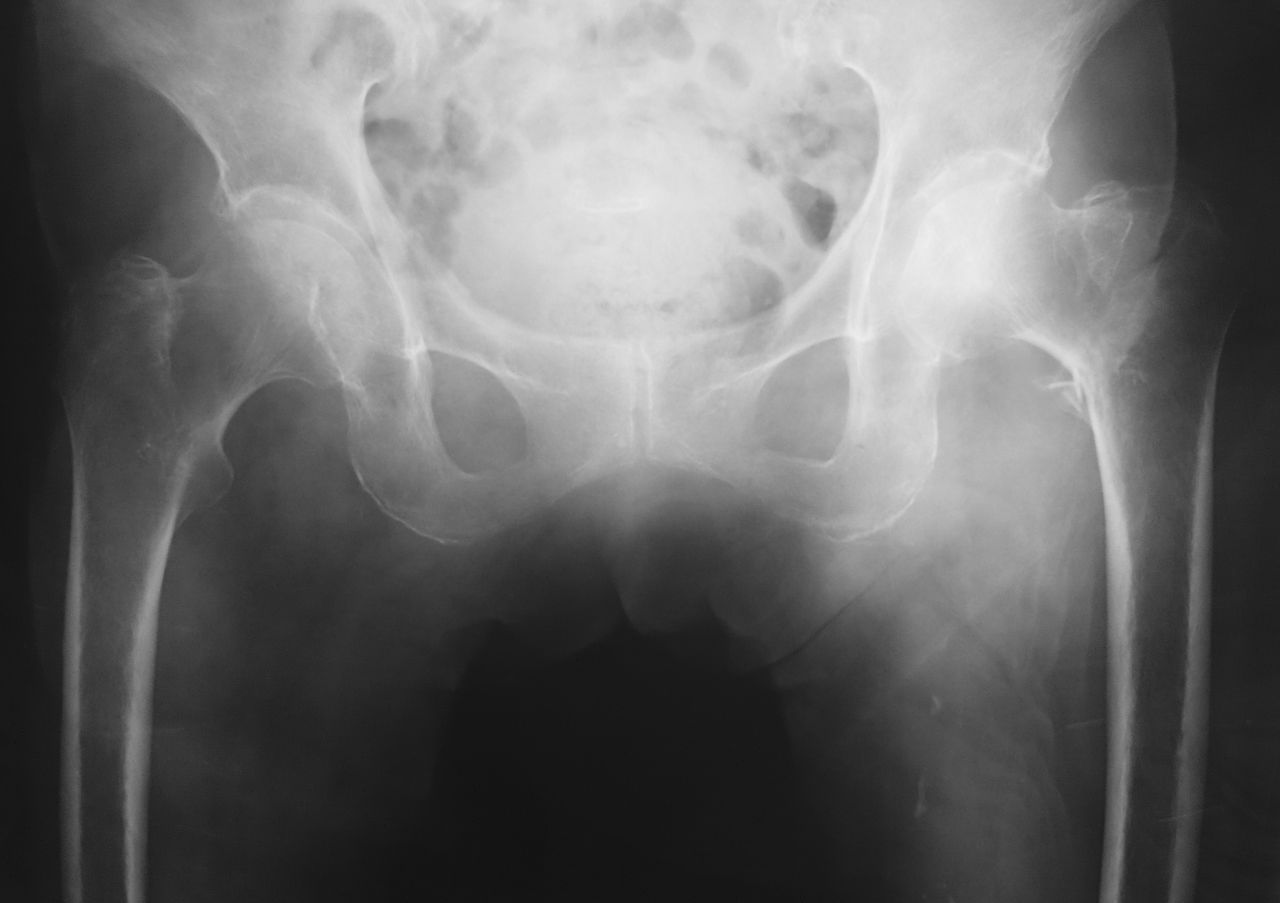

まずは新潟大学の遠藤直人教授の骨粗鬆症に関する講演です。大腿骨近位部骨折の予防で重要なことは、「骨折の連鎖」を絶つことだそうです。骨折の連鎖とは下記の3つです。

1. 脊椎椎体骨折 ⇒ 大腿骨近位部骨折

2. 大腿骨近位部骨折 ⇒ 反対側の大腿骨近位部骨折

3. 母 ⇒ 娘

1 は、脊椎椎体骨折が発生すると身体のバランスが悪くなり転倒リスクが増大するため、大腿骨近位部骨折を併発しやすくなるそうです。2 もほぼ同様の理由で反対側の大腿骨近位部骨折を併発しやすくなります。

3 は、親子(母娘)の骨質は非常に似ているため、大腿骨近位部骨折をおこした方の娘にも、高率に大腿骨近位部骨折が発生する傾向があるそうです。